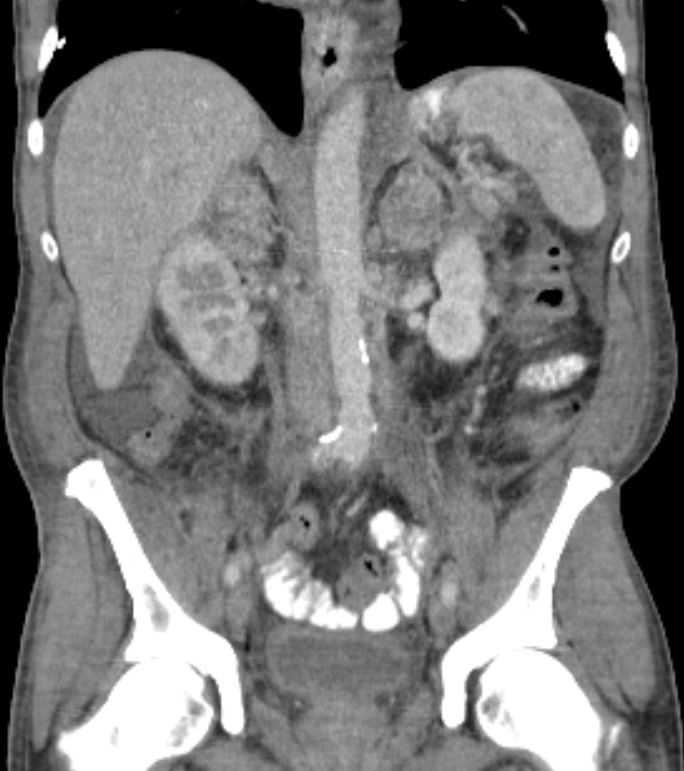

50-jähriger Mann mit primär hepatisch und

pulmonal metastasiertem Antrumkarzinom.![]() | |